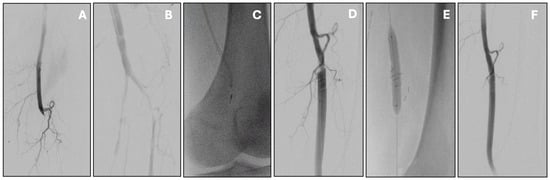

The Indigo Aspiration System functions by delivering continuous aspiration through a high-efficiency catheter, allowing for clot removal in a single-pass or multiple-pass technique. The system is designed to be flexible and trackable in torturous anatomy, making it suitable for peripheral interventions. Recent generations of the Indigo system have integrated artificial intelligence–driven clot detection and flow optimization algorithms. These innovations enable real-time adjustment of suction power and catheter positioning, potentially improving procedural efficiency and reducing time to revascularization. (Figure 2).

Figure 2. Acute infrainguinal bypass occlusion managed by percutaneous mechanical thrombectomy with the Indigo Penumbra system. Initial angiography showed popliteal graft thrombosis (A) with distal re-opacification of the popliteal artery (B). Mechanical thrombectomy was carried out with multiple passes of the Indigo Penumbra system (C), resulting in effective thrombus removal. This also uncovered a proximal anastomotic stenosis (D), which was subsequently treated with stenting (E). Final angiography confirmed good patency of the treated segment without residual stenosis or thrombus (F).